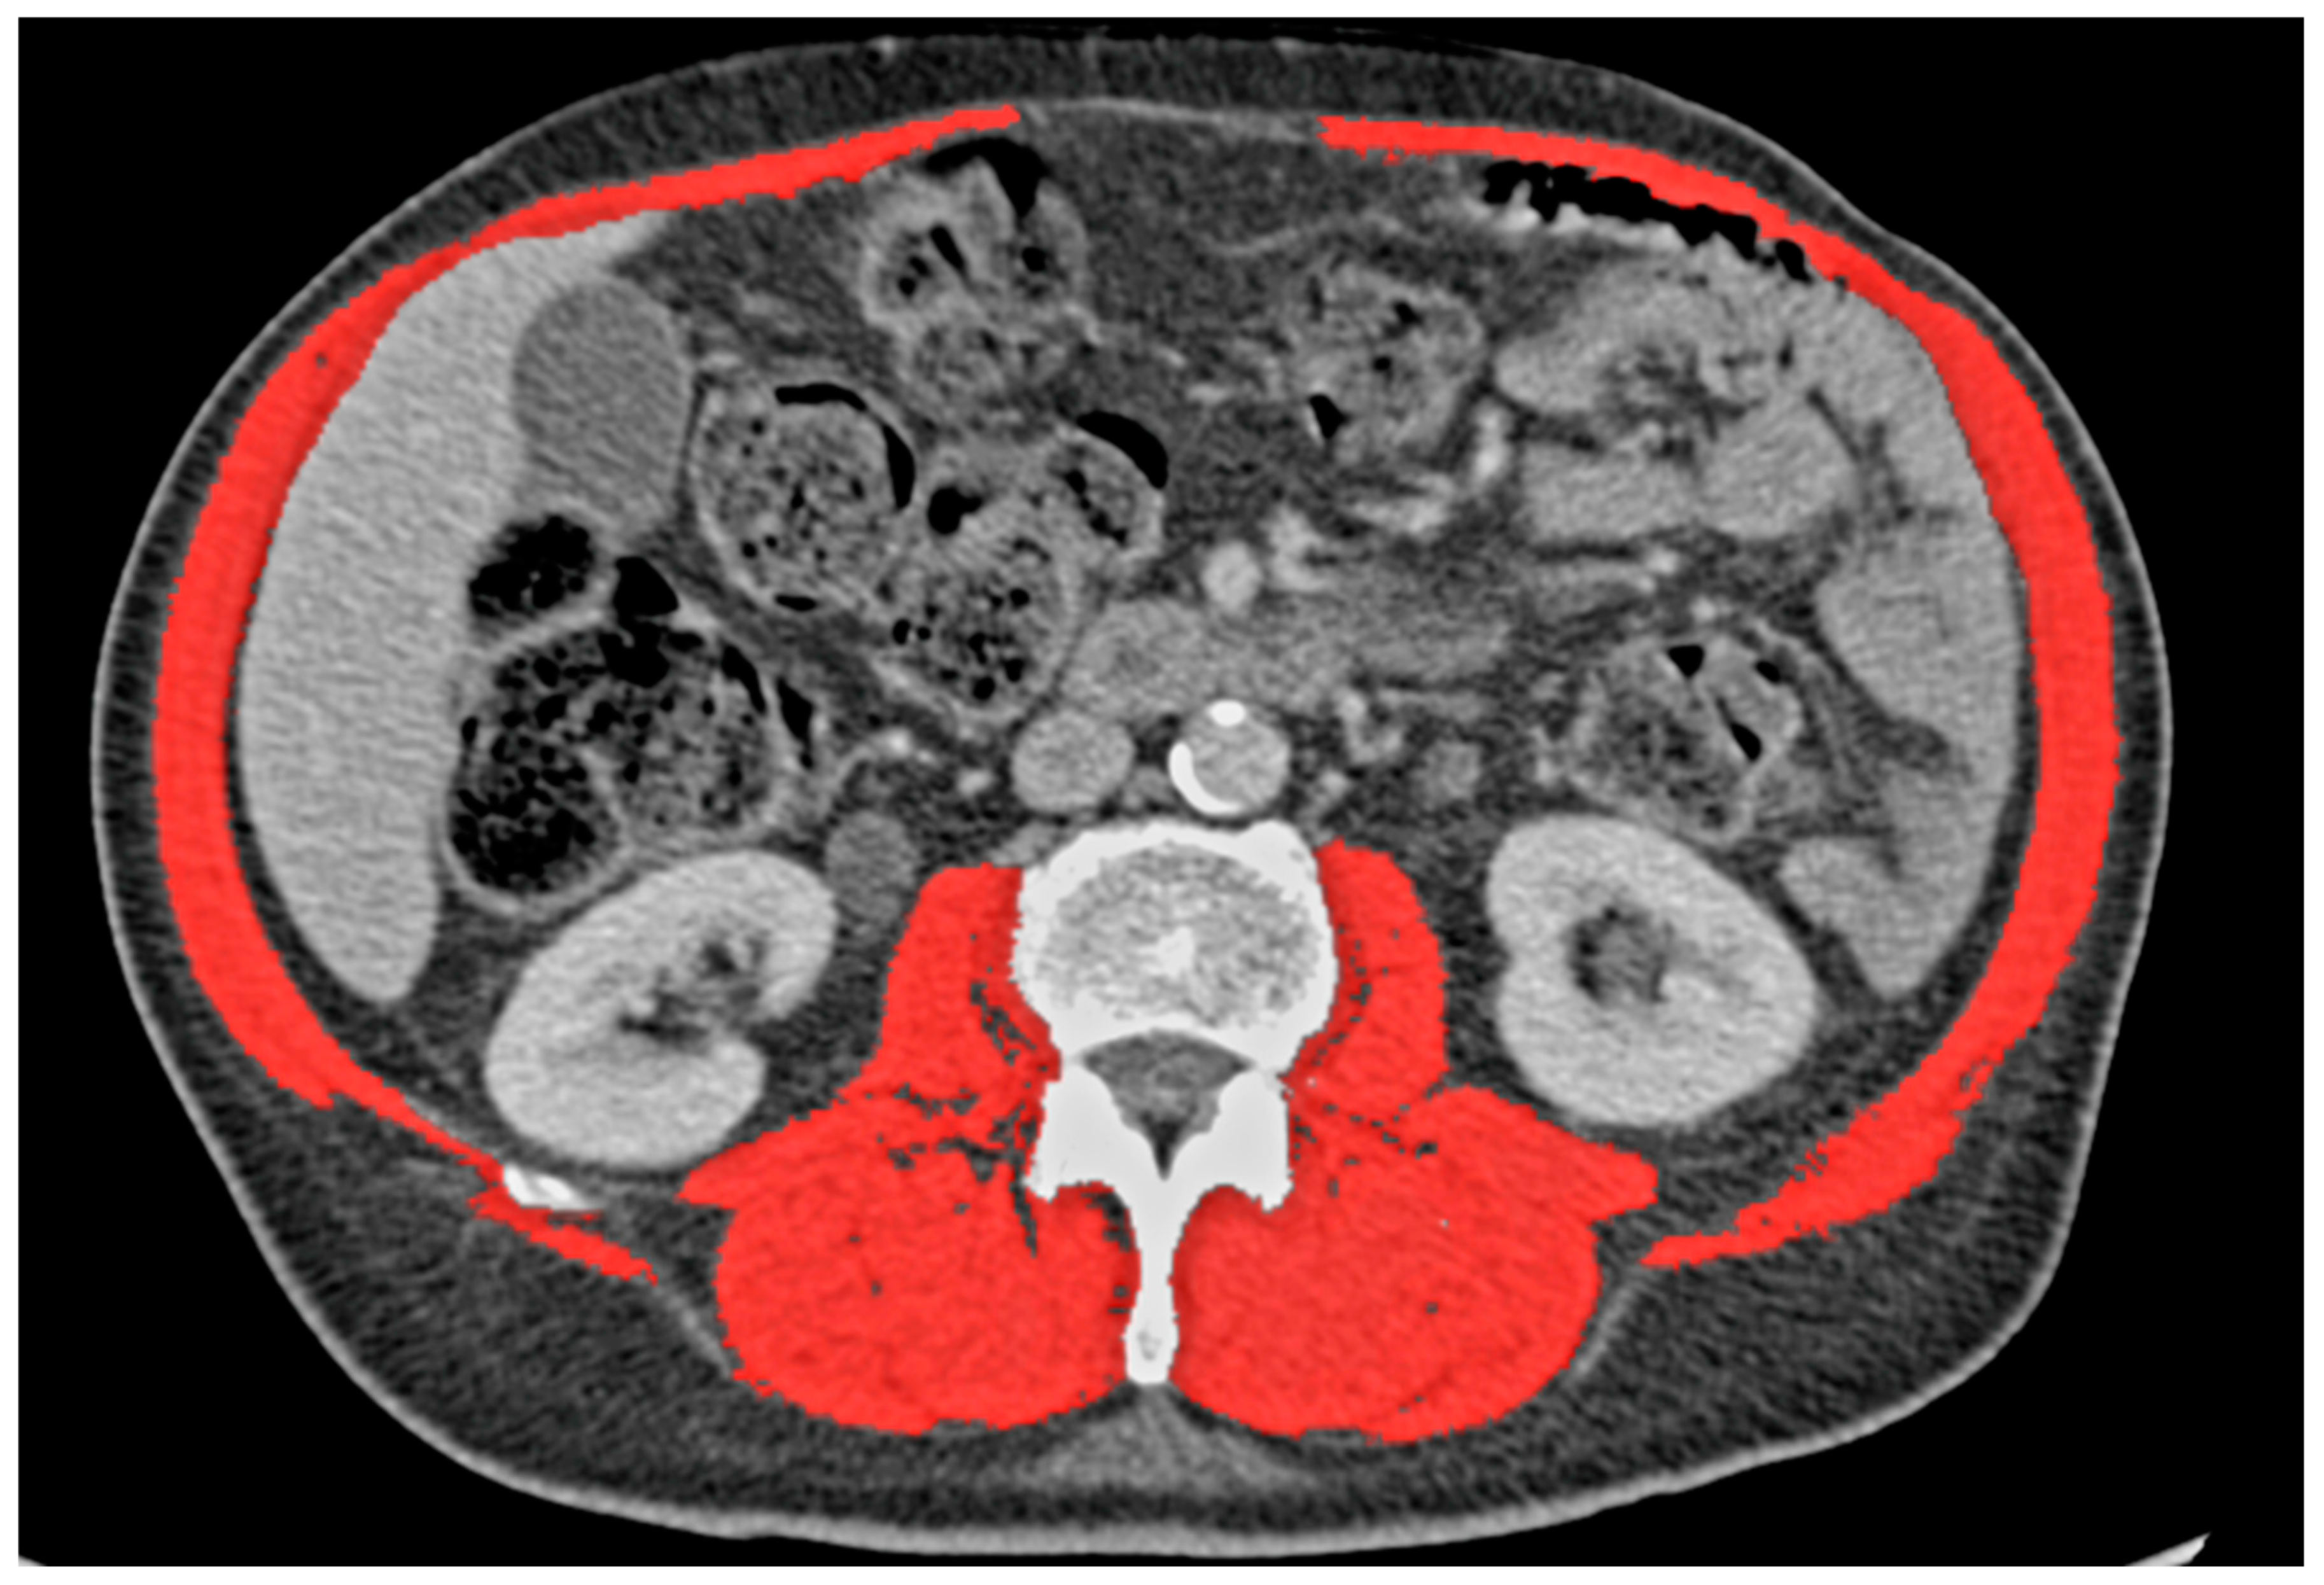

2.3. Definitions

3.1. Skeletal Muscle Index

3.2. Mediastinal Adipose Tissue